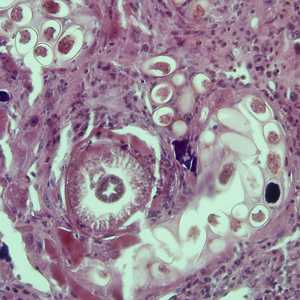

July - 2008 - Case #232

A study was conducted on herding dogs in a sheep-raising region of northeastern Arizona to determine the prevalence of Echinococcus granulosus. Public health officials wanted to determine the risk for hydatid cyst disease in the local people.